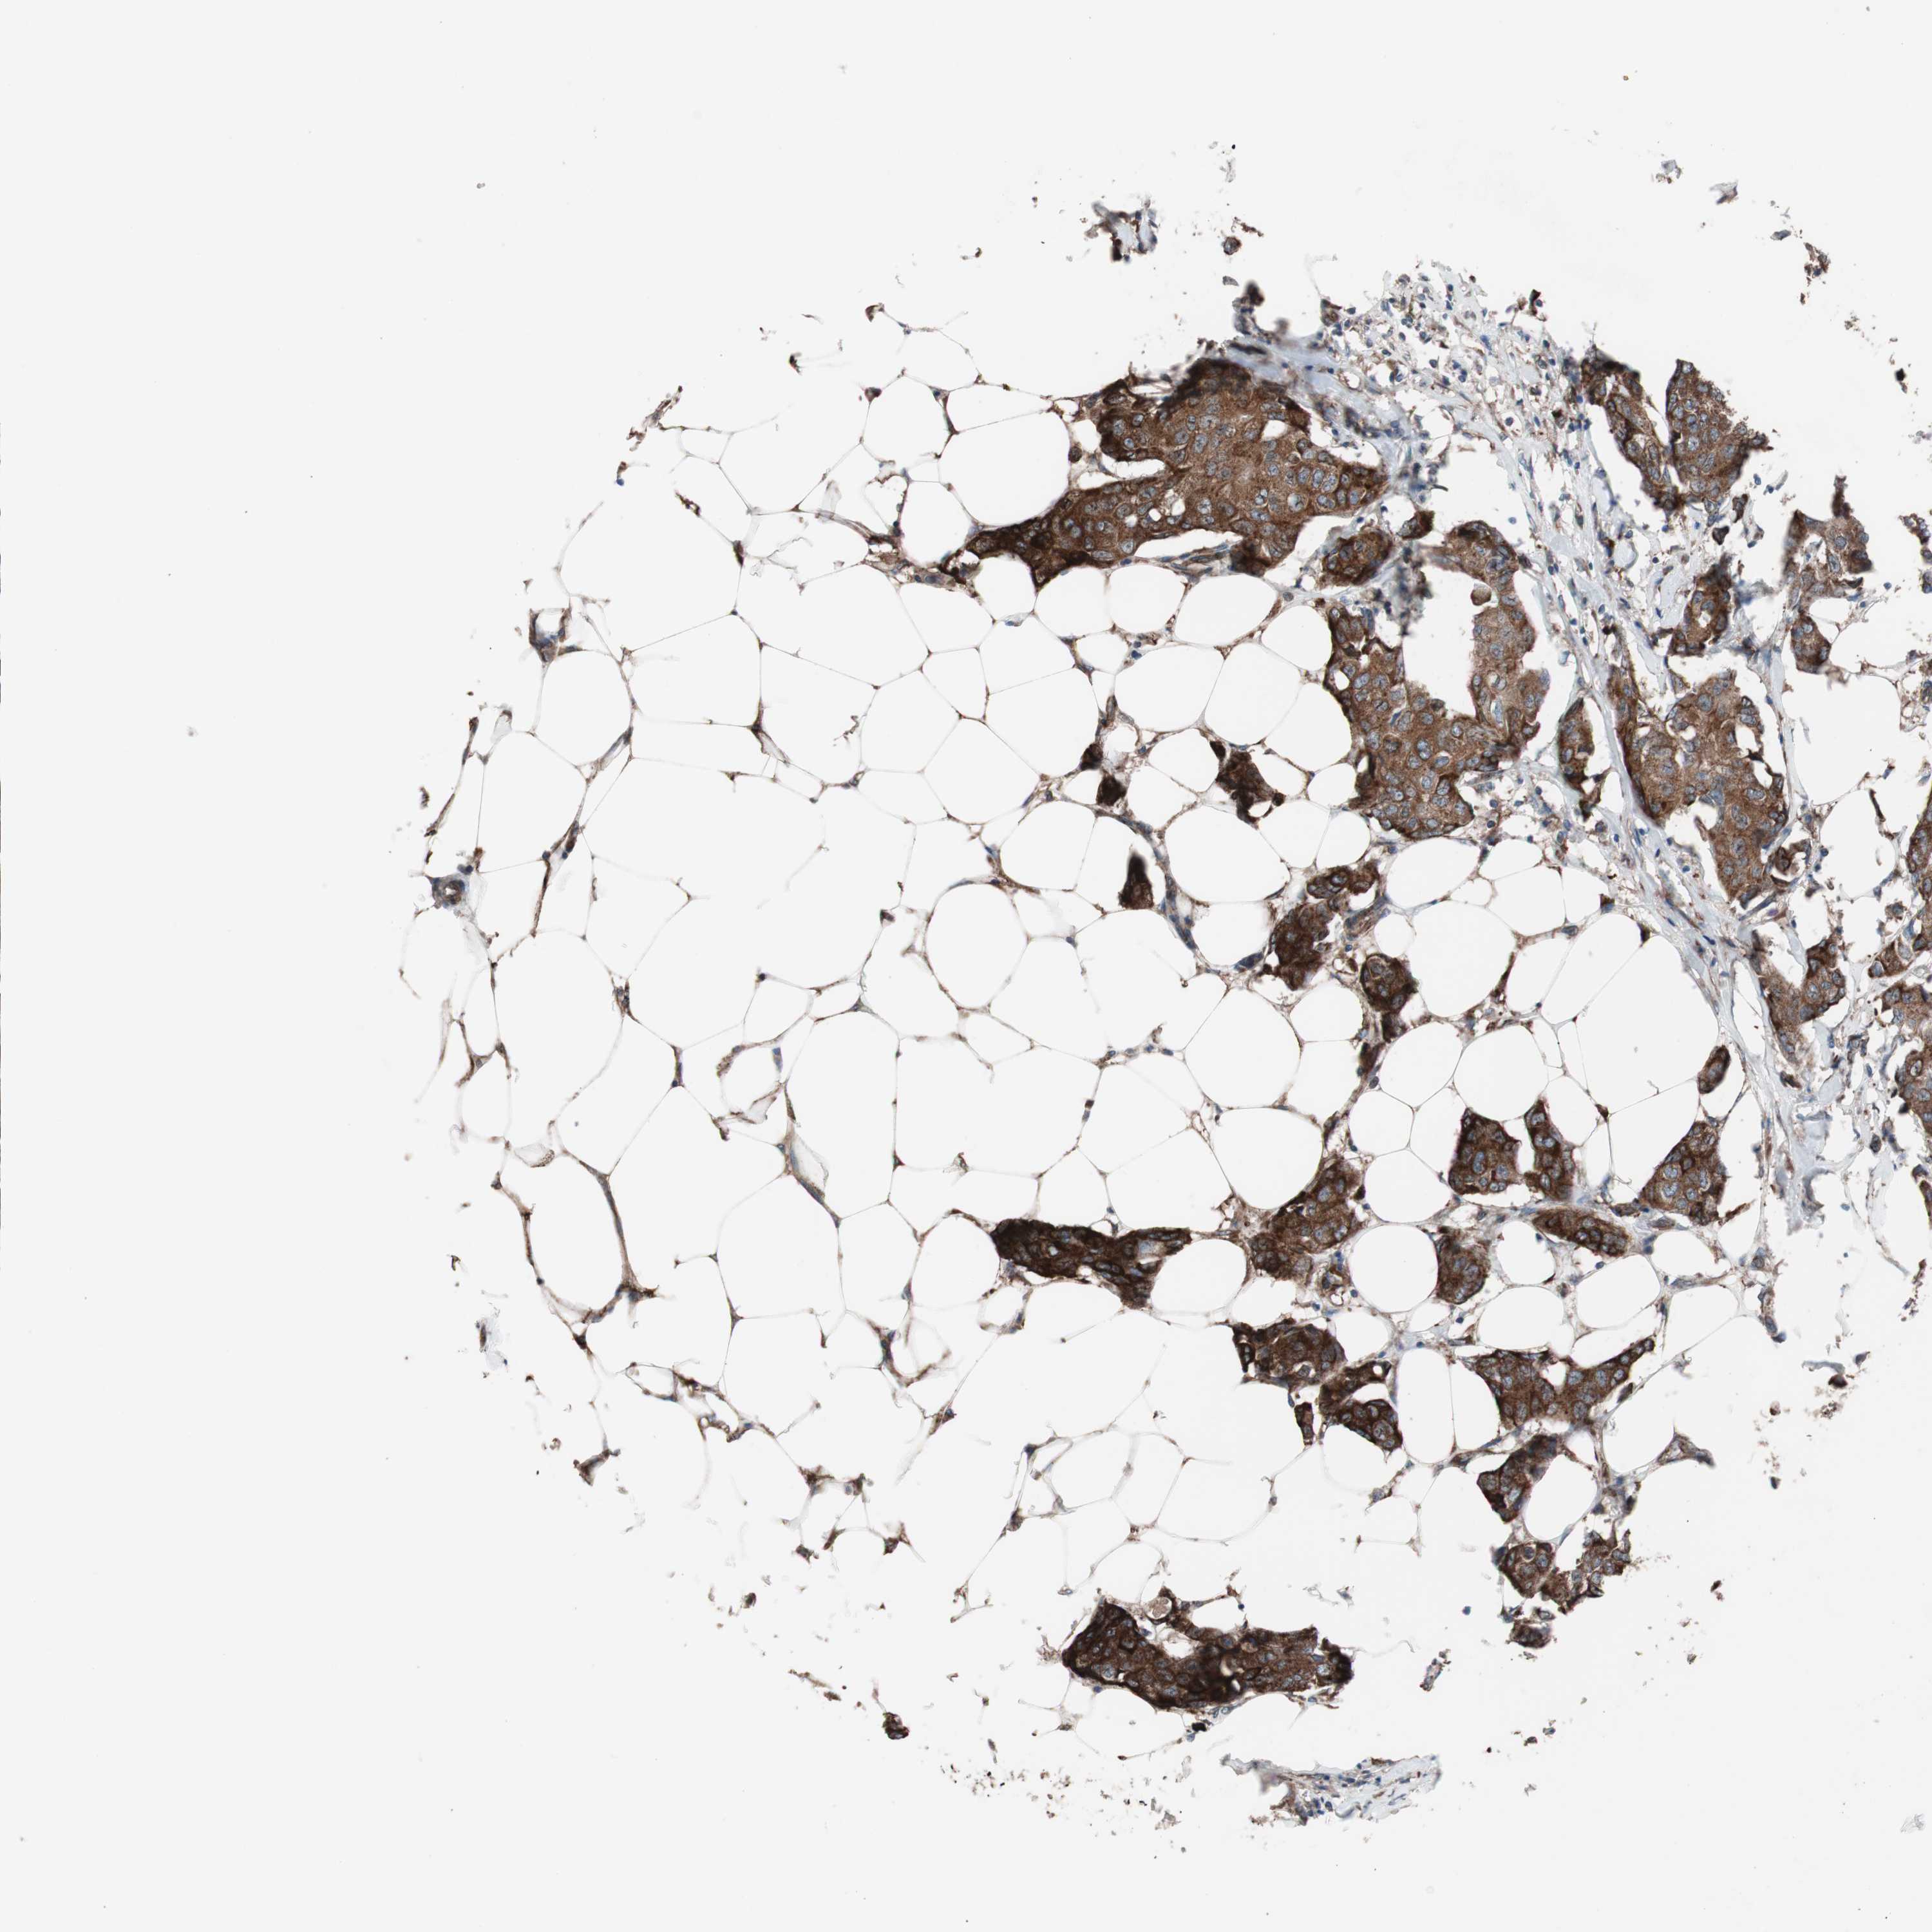

CANCER BREAST CANCER Show tissue menu

BRCA TCGA BRCA VALIDATION PROTEIN EXPRESSION

Breast cancer

Human cancer

Breast invasive carcinoma